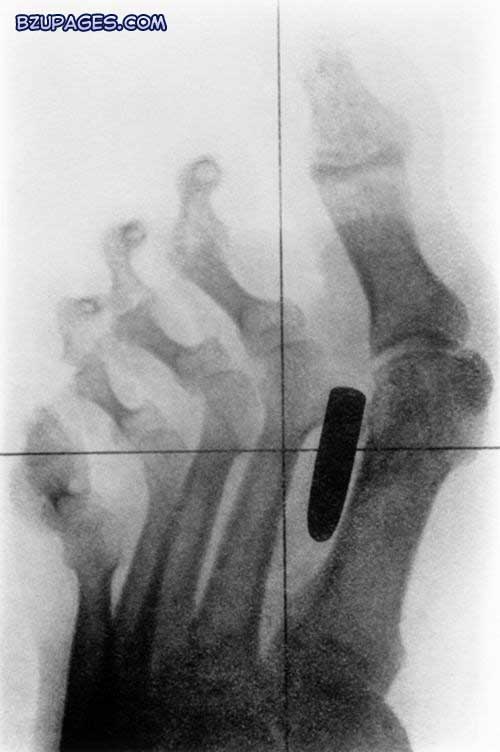

The comical yet disturbing results are taken from hospitals around the world and show how accidents come in all shapes and sizes. This X-ray shows a nail (upper centre) lodged in bones of the index and middle fingers of an adult male, having penetrated through the skin